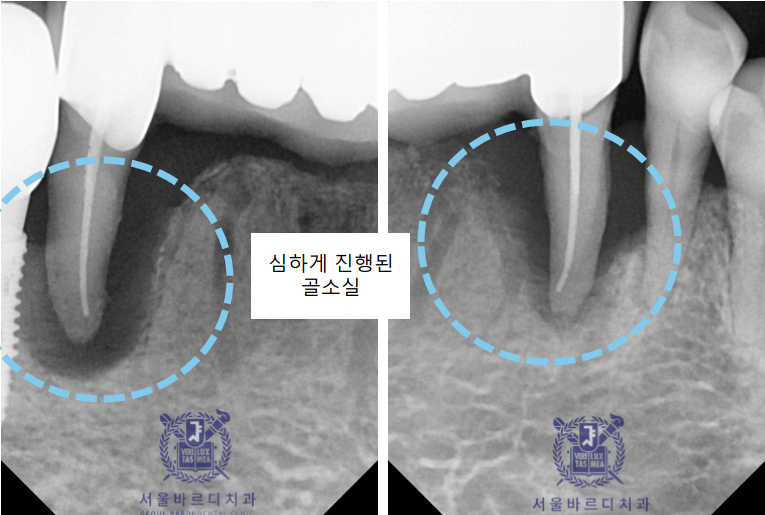

앞니쪽은 조금 더 자세하게 보기위해 치근단 엑스레이를 추가로 촬영하였습니다.

양쪽 송곳니 두개를 이용해 앞니 6개의 보철을 사용하고계셨는데

지지해주던 양쪽 송곳니쪽에 문제가 생겨서

염증이 이미 많이 진행된 상태였습니다.

치주염이 원인인데요,

치주염은 중증으로 발전된 치은염으로,

잇몸의 염증이 치아의 지지 구조까지 확대됩니다.

플라그와 치석이 치아와 잇몸 사이에 쌓인 후

치아 아래의 뼈까지 퍼집니다.

붓고 피나는 잇몸 상태가 되며, 심해지면 이가 흔들리고 구취가 나게 됩니다.

문제가 생긴 아래 앞니 부분은 이미 신경치료도 다 되어있는 상태였는데도

다시 뿌리 끝까지 염증이 생겨 결국 치아까지 많이 흔들리고,